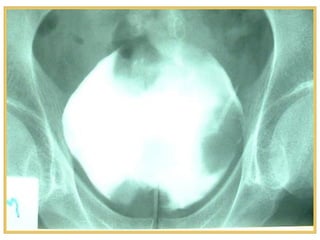

Diagnosis

• Ultrasonography: echogenic

intravesical mass

• Plain&IVU: bladder filling defect

• Pelvic and abdominal CT: confirm

and stage bladder carcinoma